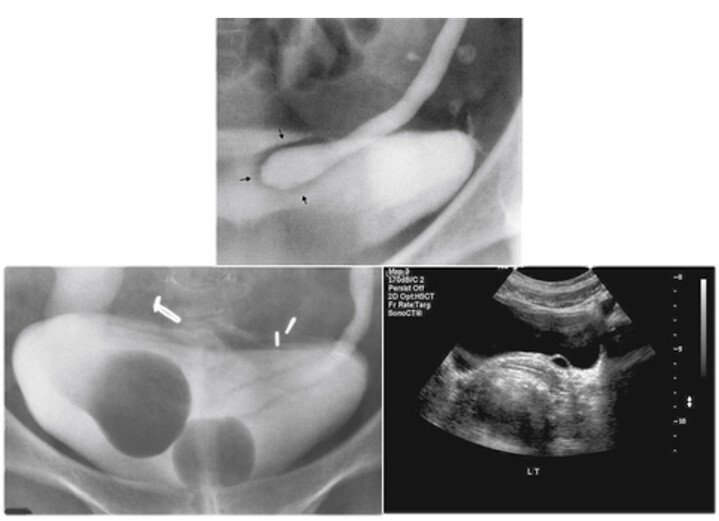

14

Q

What pathology is seen here?

A

Ureterocele

15

16